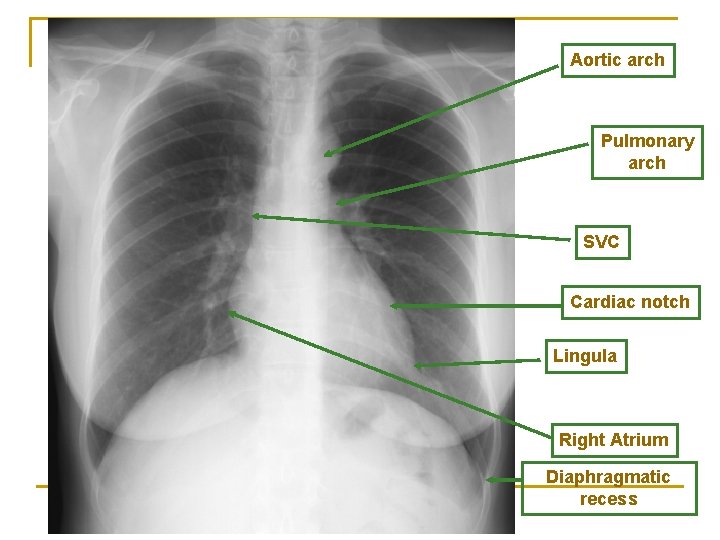

Aortic arch Pulmonary arch SVC Cardiac notch Lingula Right Atrium Diaphragmatic recess